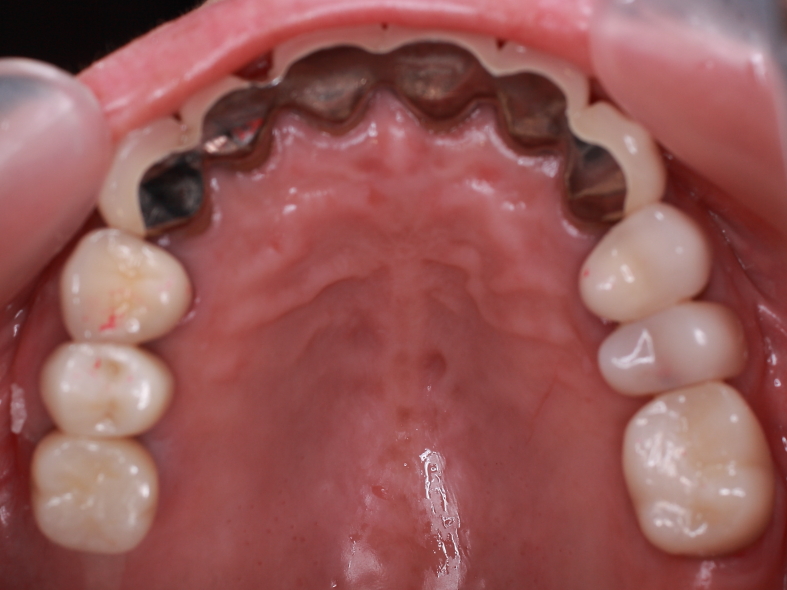

前歯の隙間を部分矯正します。

4前歯にブラケットを装着します。

3ヶ月程で隙間が無くなりました。

イメージが大分変りますネ。